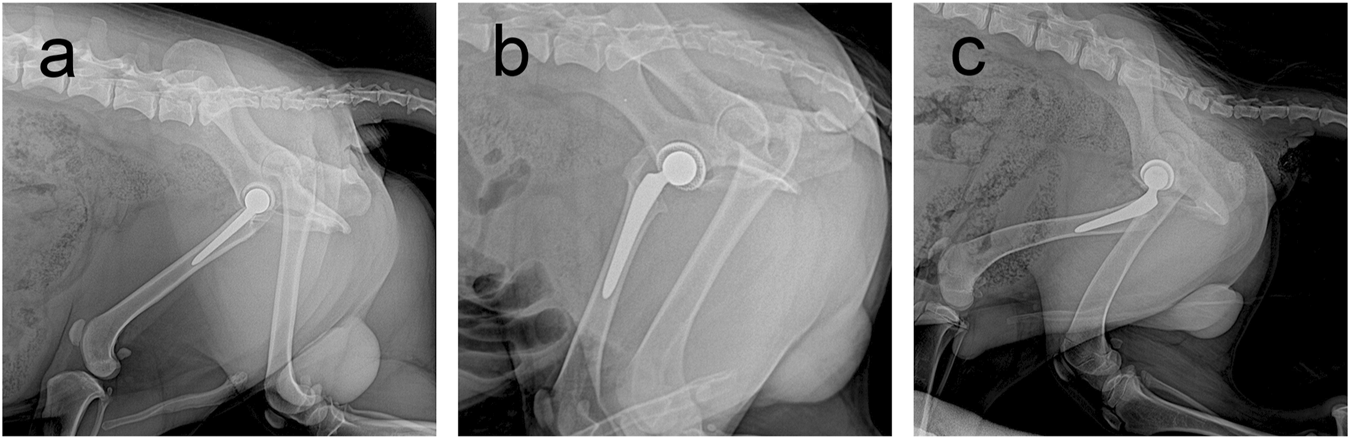

At the final follow-up, the X-ray film confirmed that the prosthesis was in a normal position, and no obvious dislocation or loosening was observed (Figure 4). Owing to numerous pores, the porous acetabular cup showed a slightly higher transmittance under X-rays than the HA-coated cup. No transparent zone was observed around the three groups of acetabular cup prostheses. A slight increase in bone density was observed at the top of the femur and acetabulum, and there was no significant difference in bone density around the three groups of prostheses (p > 0.05).

FIGURE 4

Follow-up X-rays of prostheses of three materials at 6 months postoperatively. Prosthesis can be seen in a good position, with no obvious loosening and dislocation and other performance. (A) Sintered porous titanium alloy acetabular cup groups; (B) 3D-printed porous titanium alloy group; (C) HA-coated titanium alloy acetabular cup group.